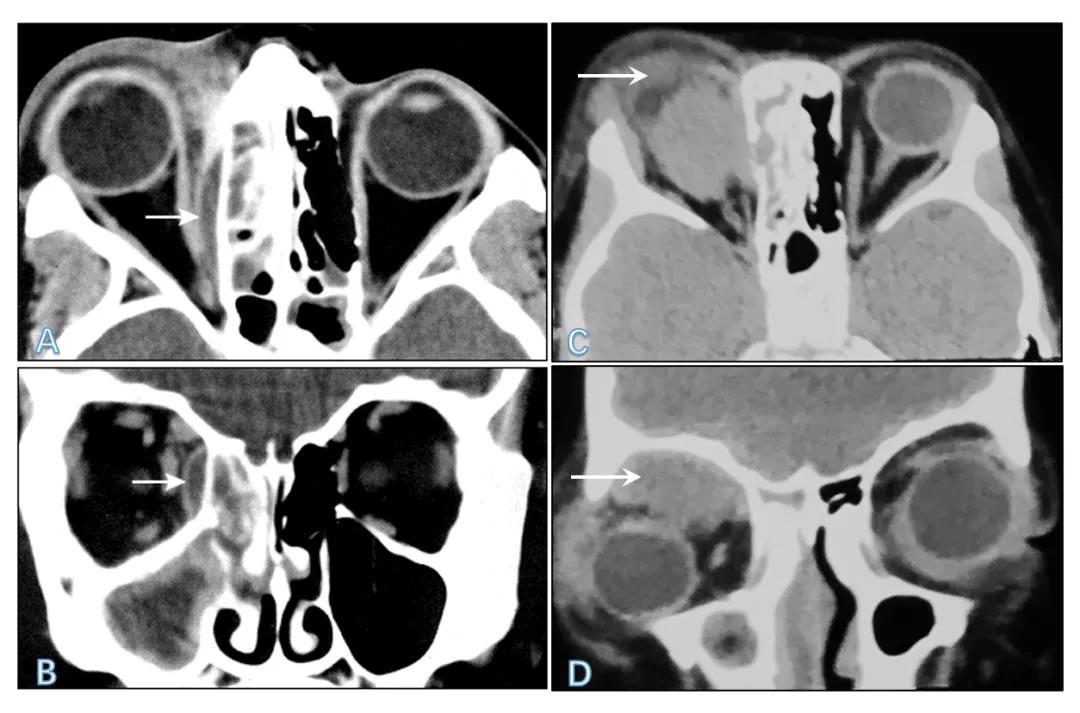

(2)影像学检查:①鼻窦及眼眶CT是儿童眼眶蜂窝织炎临床诊断及鉴别诊断的必要依据,具有重要临床意义。可以协诊病变范围和程度、毗邻骨壁和眼外肌累及情况、鼻窦炎程度及其与眼眶感染的关系,显示脓肿形成及部位,提示切开排脓的手术时机、方法、路径等。应作为常规检查方法。眶骨膜下脓肿和眶内脓肿在CT片上表现为低密度积液,常邻近筛窦。骨膜下脓肿位于骨膜和骨性窦壁之间(图4A)。②眼眶MR显示眶内软组织较CT好,但对于眶壁骨质改变不如CT 敏感和准确。③眼彩超简便迅速,眶内脓肿彩超表现为不规则暗区。

图4 眼眶和鼻窦CT:图4A眼眶软组织窗横断位,图4B冠状位,箭头示眶内侧壁骨膜下脓肿;图4C横断位,图4D冠状位,箭头示眶内脓肿,位于右侧眼眶上象限肌锥外间隙(源:图4A,4B Copyright © 2004 Lippincott Williams &Wilkins.图4C,4D源自本患儿影像资料.)